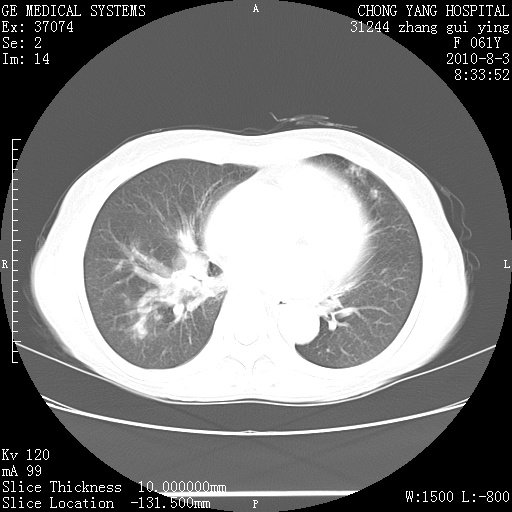

标题: CT28314:F61Y胸部增强,发热咳嗽一周入院,后面的为一周前平 [打印本页]

标题: CT28314:F61Y胸部增强,发热咳嗽一周入院,后面的为一周前平

1、支持考虑右侧中央型肺癌伴右肺中叶节段性不张及下叶支气管黏液痰栓    2、左肺上叶舌段感染。

双肺感染性病变,不除外合并结核感染。

确切的说:1:右肺下叶中心型肺癌侵及中叶支气管并中叶不张,纵膈淋巴结转移。2:左肺舌叶炎症。3:右侧胸腔少量积液